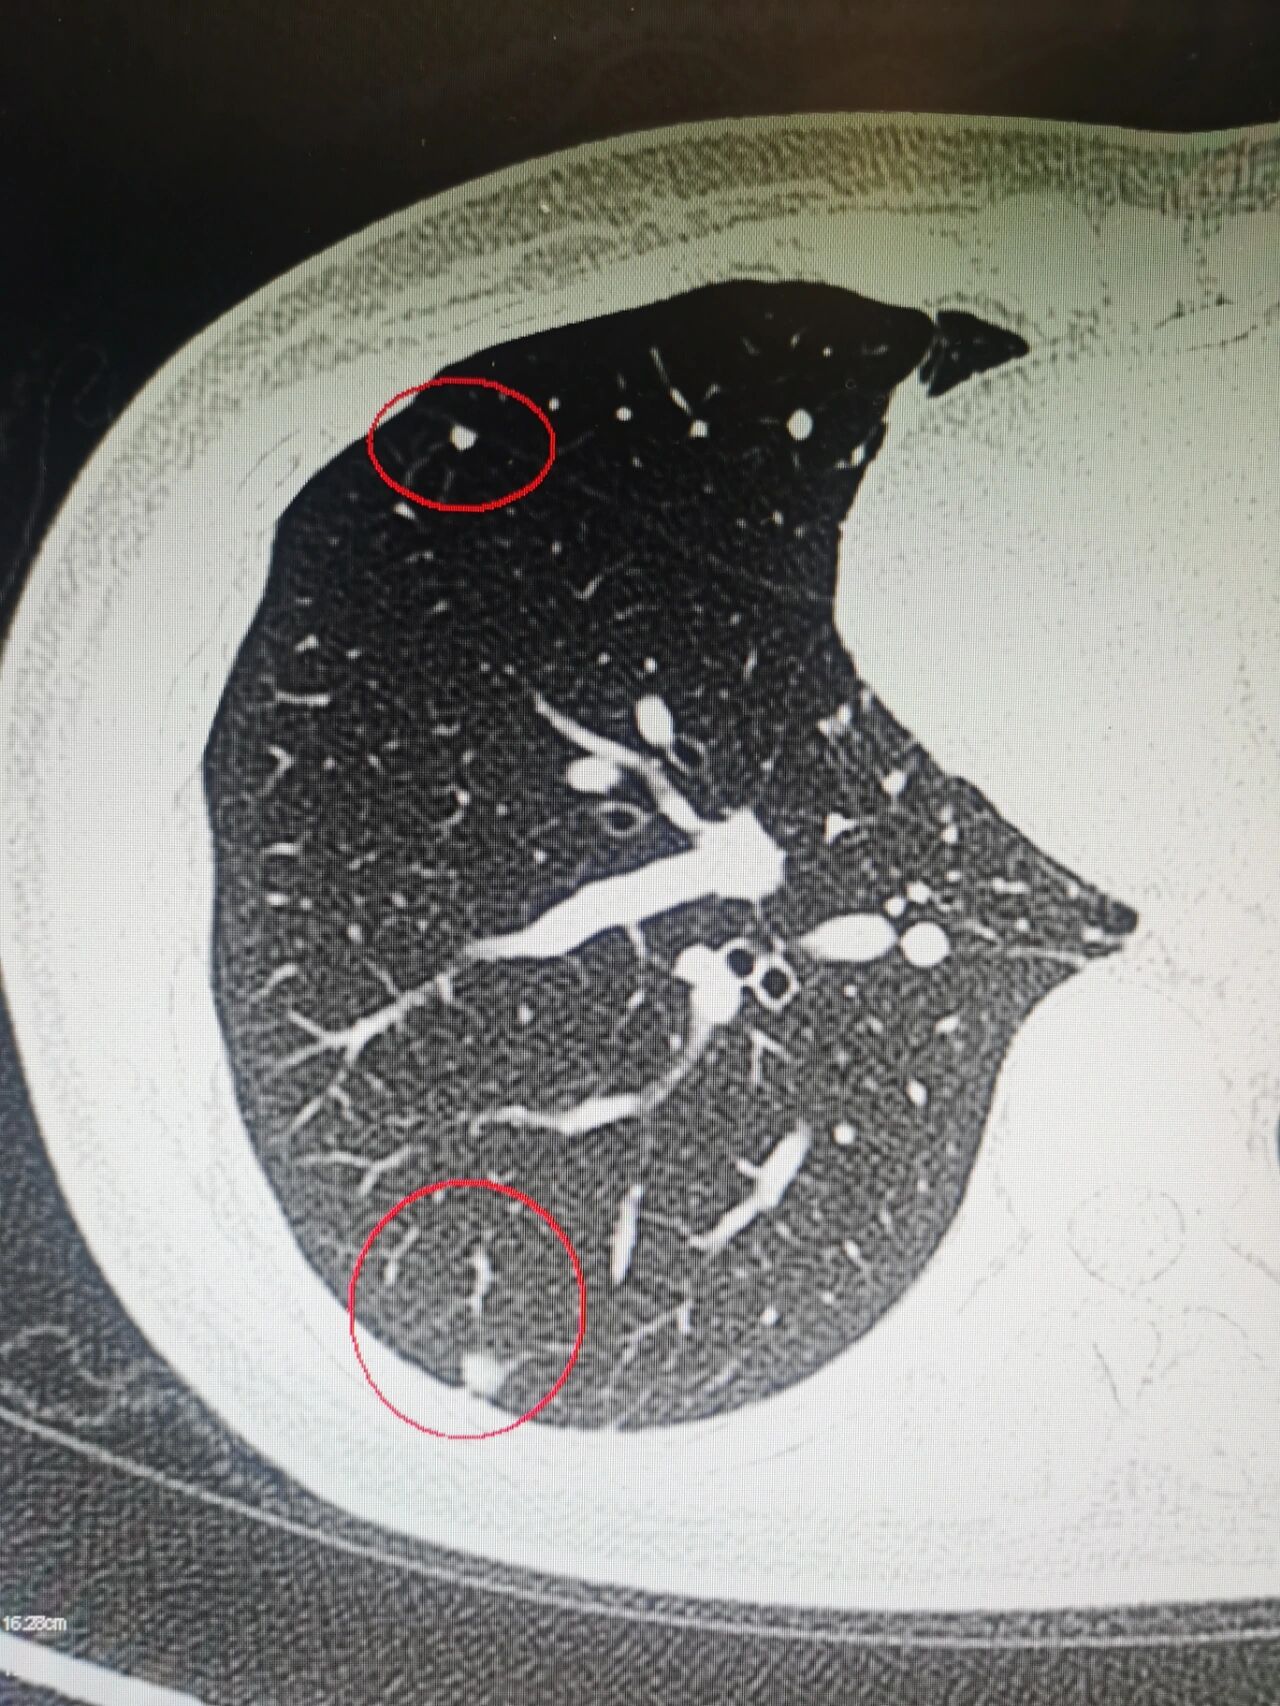

分享一种良性肺结节 湖南湘雅 分享良性 的中的一种肺内淋巴结 ,一旦